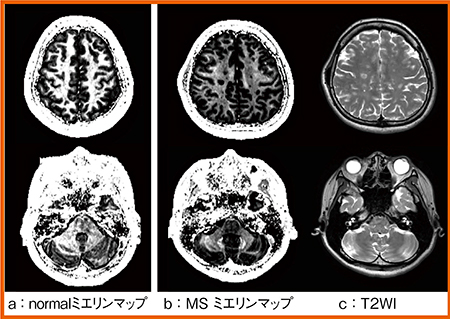

本症例に対しQPMを追加し,定量値からミエリン(髄鞘)に相当する画像を作成した。ミエリン量は,r1に比例し,T2値に反比例して10〜20msと短いことが知られている。そこで,r1,r2マップから髄鞘密度強調マップ(ミエリンマップ)を作成した(図1)。

正常例のミエリンマップ(図1 a)では,白質部分が非常に高信号に描出されるが,本症例ではミエリンの減少(脱髄)により,プラーク部分がほぼ信号欠損として描出された(図1 b)。また,T2強調画像(図1 c)では,プラーク周辺の白質の信号に異常は認められないが,ミエリンマップ(図1 b)では不均一な信号低下が認められた。これはnormal appearing white matterを反映していると考えられる。さらに,ルーチン画像では異常を認めない小脳においても,ミエリンマップでは不均一な信号低下があり,臨床所見と一致する変化が示唆された。ただし,ミエリンマップでは短いT2の成分を強調するため,金属沈着の影響も反映し,黒質や歯状核などは高信号となることを考慮する必要がある。

図1 症例1:ミエリンマップとT2強調画像